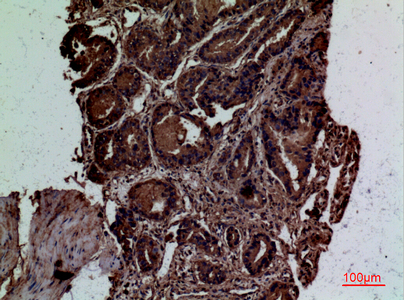

| IHC | 1/50-1/100 |